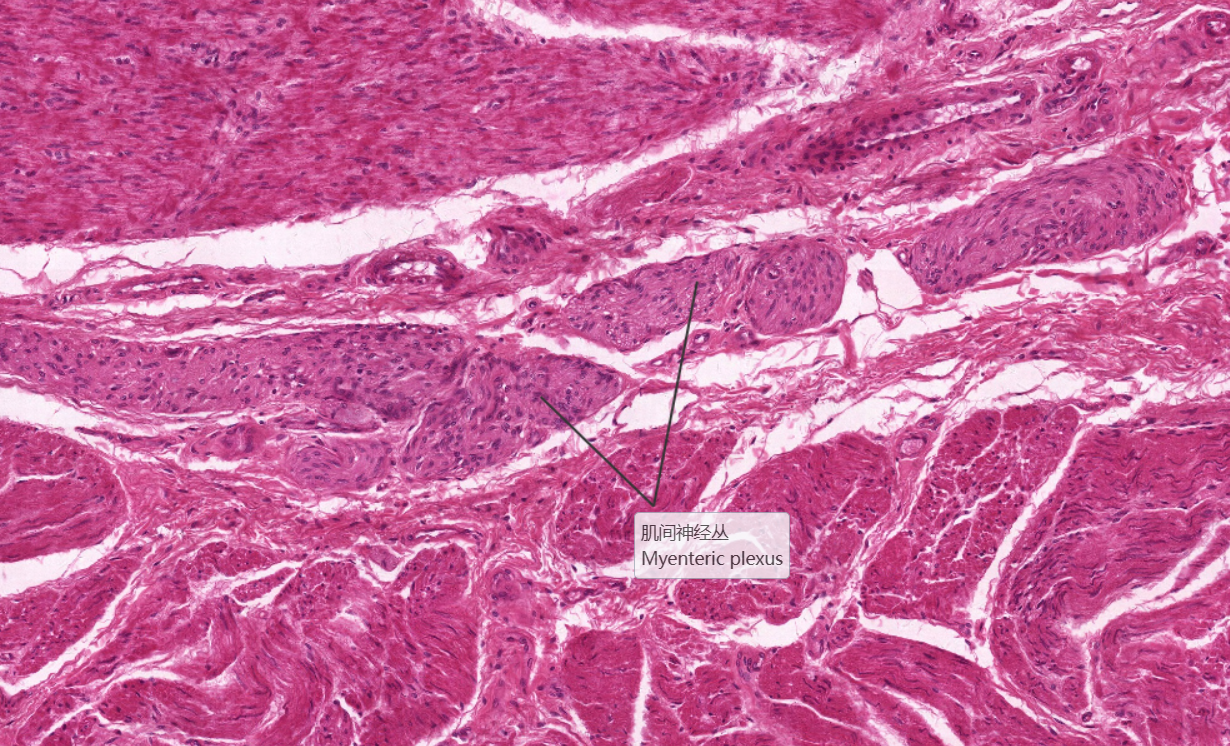

还有较大的血管。此外,此层可见有黏液性的复管泡状的食管腺。3、 肌层:该片取自食管上三分之一部分,

为骨骼肌。可分为两层,两层之间的结缔组织内有肌间神经丛。

6.肌间神经丛